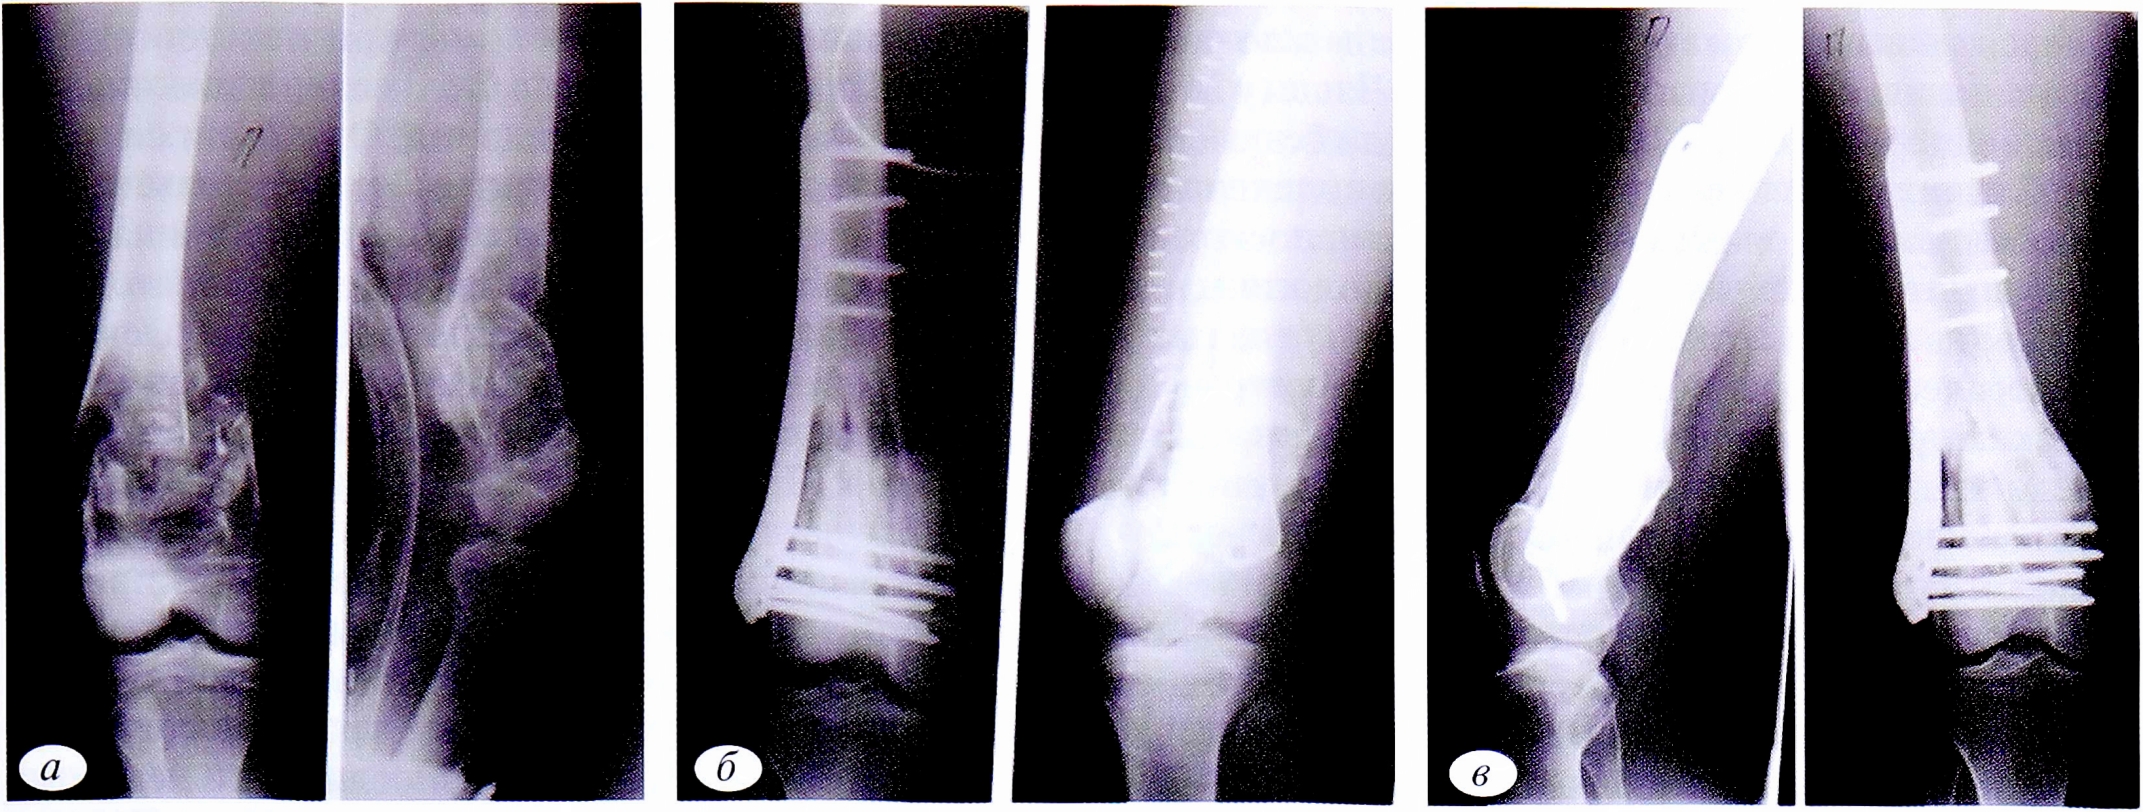

Рис. 3. Пациент К.,18 лет. Диагноз: патологический перелом дистального отдела правой бедренной кости со смещением отломков на фоне аневризмальной кисты. а — рентгенограммы правой бедренной кости в 2 проекциях до операции; б — в 2 проекциях после операции: открытая репозиция, краевая резекция дистального отдела правой бедренной кости, аллопластика ЗКТ, фиксация пластиной и винтами; в — в 2 проекциях через 18 мес: рентгенологически отмечаются консолидация перелома, неорганотипическая перестройка трансплантатов, признаков рецидива заболевания не наблюдается.

Fig. 3. Patient К.,18 years old. Diagnosis: pathological fracture of the distal part of the right femur with displacement of fragments on the basis of aneurysmal cyst. a — radiographs of the right femur in 2 projections before surgery; б — radiographs of the right femur in 2 projections after surgery: open reduction, marginal resection of the distal part of the right femur, alloplasty of the CT, fixation with a plate and screws; в — radiographs of the right femur in 2 projections result after 18 months. X-ray consolidation of the fracture, inorganotypic restructuring of the grafts is noted. There are no signs of relapse.